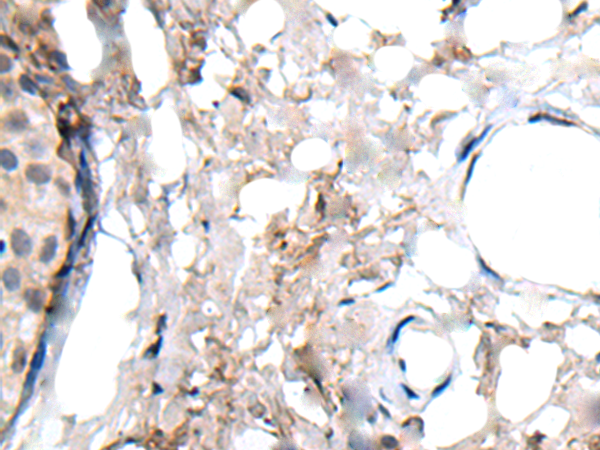

IHC positive control:

Human liver cancer and human lung cancer

IHC Recommend dilution:

25-100